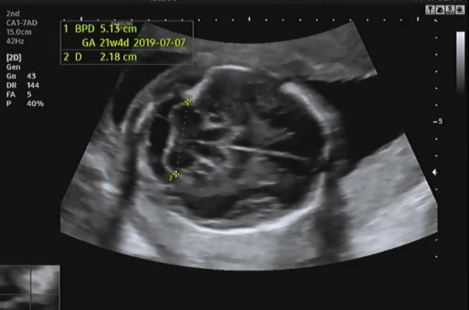

그다음 태아의 머리 둘레를 측정하고 21주 차에 맞게 뇌가 주수에 알맞게 발달하였는지, 물혹 등의 여부나 기형이 있는지 확인을 한다.